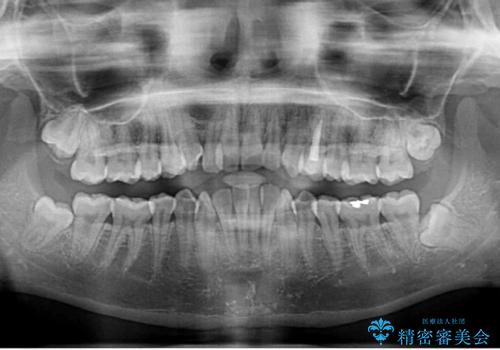

- 前歯のクロスバイトを気にして来院された患者様です。

- 症状により、抜歯が必要な場合があります